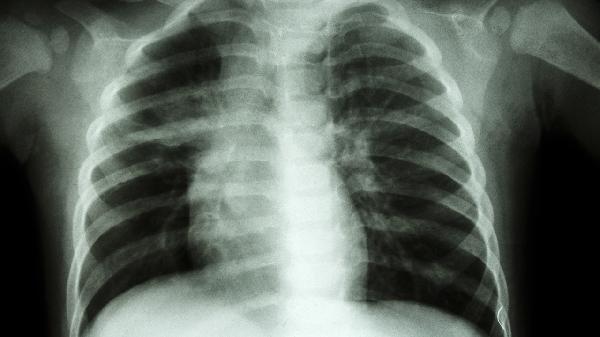

肋骨骨折常由外力撞击或骨质疏松引起,疼痛呈尖锐刺痛且随体位变化,可能伴随皮下淤血、骨擦音。需通过X线确诊,轻度骨折可佩戴肋骨固定带,遵医嘱使用洛索洛芬钠片、氨酚羟考酮片缓解疼痛。恢复期需保持呼吸道通畅,避免肺部感染。

胸膜炎多继发于肺炎、结核等疾病,疼痛随呼吸运动加重,可能伴随发热、咳嗽。需通过胸片或CT明确病因,细菌性胸膜炎可遵医嘱使用头孢呋辛酯片、左氧氟沙星片等抗生素。急性期应卧床休息,采取患侧卧位减轻疼痛。